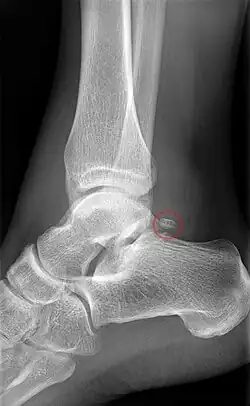

Fracture

The talus bone lacks a good blood supply. Because of this, healing a broken talus can take longer than most other bones. One with a broken talus may not be able to walk for many months without crutches and will further wear a walking cast or boot of some kind after that.

Talus injuries may be difficult to recognize,[9][10] and lateral process fractures in particular may be radiographically occult. If not recognized and managed appropriately, a talus fracture may result in complications and long-term morbidity. A 2015 review came to the conclusion that isolated talar body fractures may be more common than previously thought.[4]

A fractured talar body often has a displacement that is best visualised using CT imaging. In case a talus fracture is accompanied by a dislocation, restoration of articular and axial alignment is necessary to optimize ankle and hindfoot function.[9]